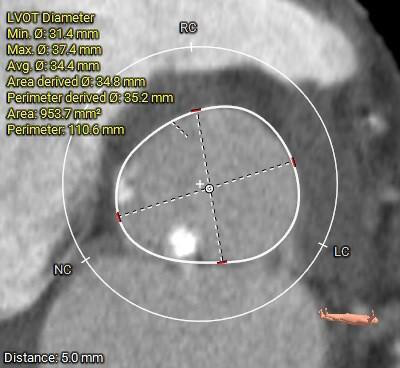

术前CT评估:

主动脉根部总览

重度钙化,分布于各窦内沿轴向延伸至窦底,无冠窦钙化延伸到LVOT水平

主动脉根部测量:

三叶式主动脉瓣,R-N疑似粘连,LVOT呈敞口型,非横位心。

三叶式主动脉瓣,R-N疑似粘连,重度钙化,分布于各窦内沿轴向延伸至窦底,无冠窦钙化延伸到LVOT水平;LVOT呈敞口型;

推荐右侧股动脉为主入路,左侧为辅助入路; 推荐23mm球囊,预装AV31瓣膜,建议瓣环下零位左右定位释放。